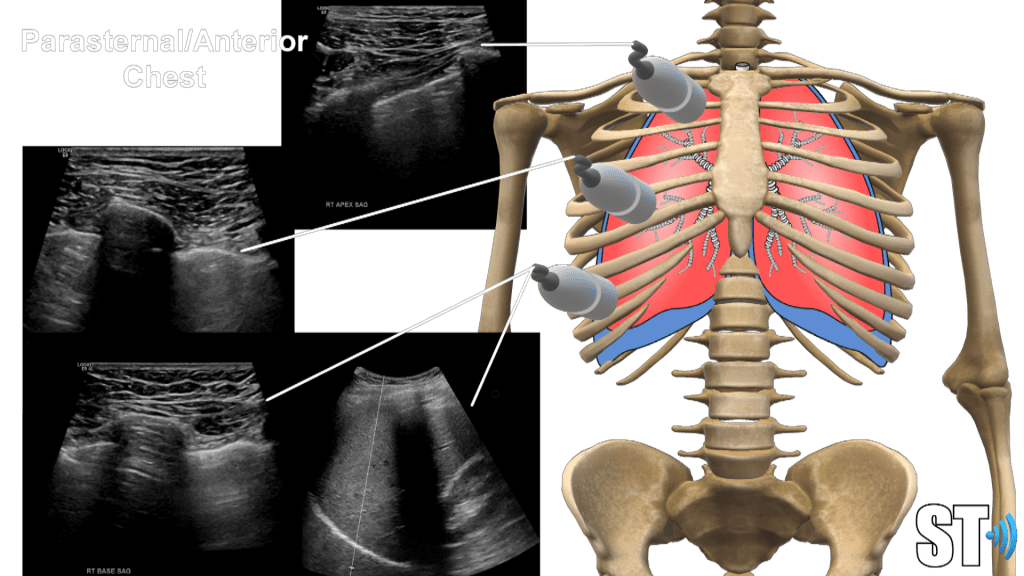

Using a linear, sector or small curvilnear transducer, divide the chest into parasternal, anterior and posterior axillary lines. Scan the basilar, mid and apical or upper portions of the chest. Scan the posterior aspect of the chest also at the base, mid and superior portions.

Anterior

Axillary

Posterior